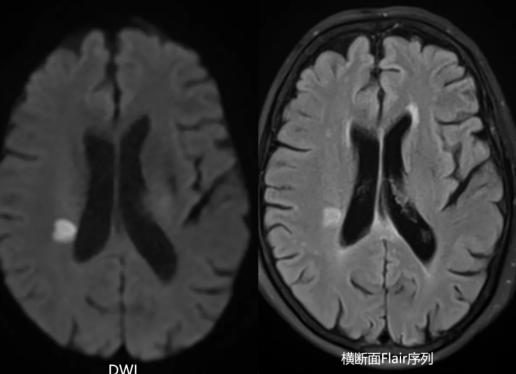

被紧急送往交大一附院神经内科后,头颅磁共振的影像冰冷地宣告:右侧基底节区急性脑梗死。如此年轻且没有“三高”等传统危险因素的患者突发中风,神内医生立刻意识到,病因绝不寻常。一场精准的“血管侦探”行动火速展开。